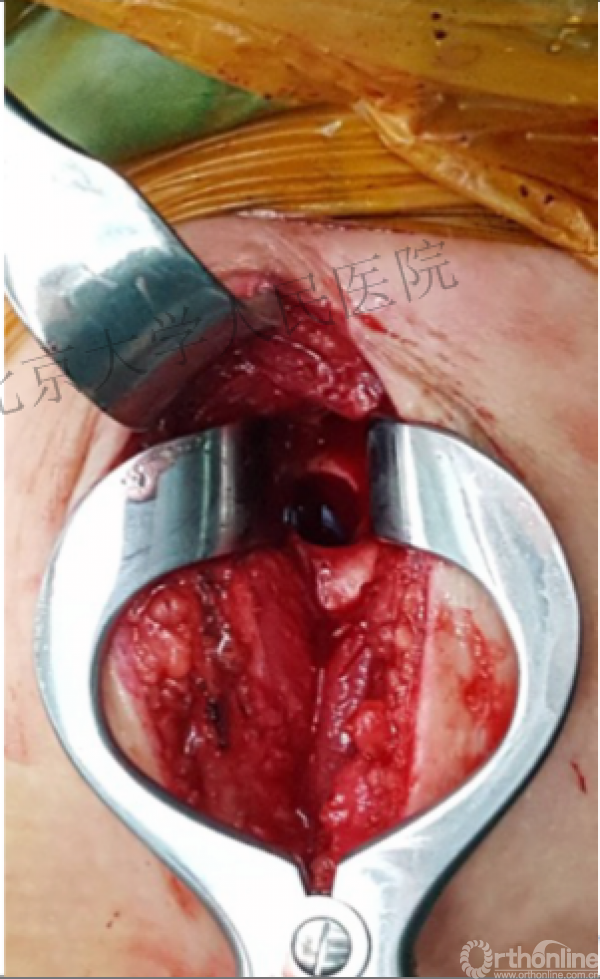

病例

可否有更好的进钉和复位的更好帮助办法?

进钉更完美——我们的帮助

术中片